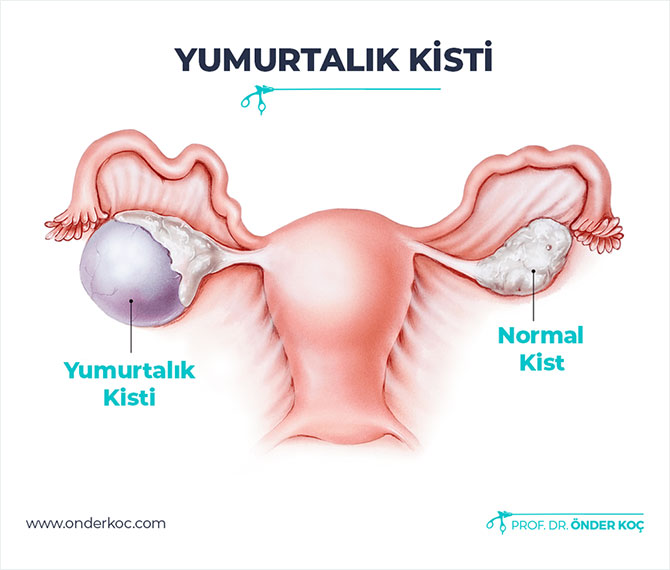

Kisti olup hamile kalanlar kist hamile kalmaya engelmidir kist varken hamile kalınırmı kist hamile kalmamda sorun yaratırmı kist ve gebelik hakkında bilgiler bazı kadınlar kistleri oldugu için bazen hamile kalmayabilir ancak 3 cm lik kisti olupta hamile kalan birsürü insan var. şubatta kontrole gideceğim umarım ben de hamile kalabilirim hayırlısıyla. Adet sancıları şiddetli olan derin cinsel ilişkide ağrısı olan karında ve kasıkta ağrıları bulunan kanlı dışkılama idrarda yanma ve kanama olması adet kanaması olduğunda burun kanaması olan vücudunda değişik yerlerde morluklar oluşan ve üreme çağında olan kadınların çikolata kisti açısından tehdit altında. çikolata kisti hamile kalmayı nasıl engeller.

Kisti olup hamile kalanlar. çikolata kisti olup sol tüpü kapalı hamile kalanlar çikolata kisti. Bunun opere olması şart değil. şubatta kontrolüm var dua ediyorum o zamana kadar hamile kalayım diye teşekkür ederim geçmiş olsun size de dermoid kistler ilaçla küçülmüyor maalesef benim de ilk dr görmemişti kisti alttan ultrasonla bakmasına rağmen 2.

Kizlar ankarada 2 devlet kadindogum hastanesi gezdim ama beni mahvettiler. çikolata kisti olup sol tüpü kapalı hamile kalanlar çikolata kisti. Merhaba kistler türüne göre gebe kalmada sıkıntı yaratır çikolata kisti de hamile kalmaya engel olan kistler den biri. Kistimin polikist oldugunu adet gorunce gectigini soylediler ve suan 2 yillik evliyim ozel hastane adini cok duydugum hulisi bulent zeynelogluna gittim dermoid kistimin oldugunu soyledi ameliyat oldum bugun 3.